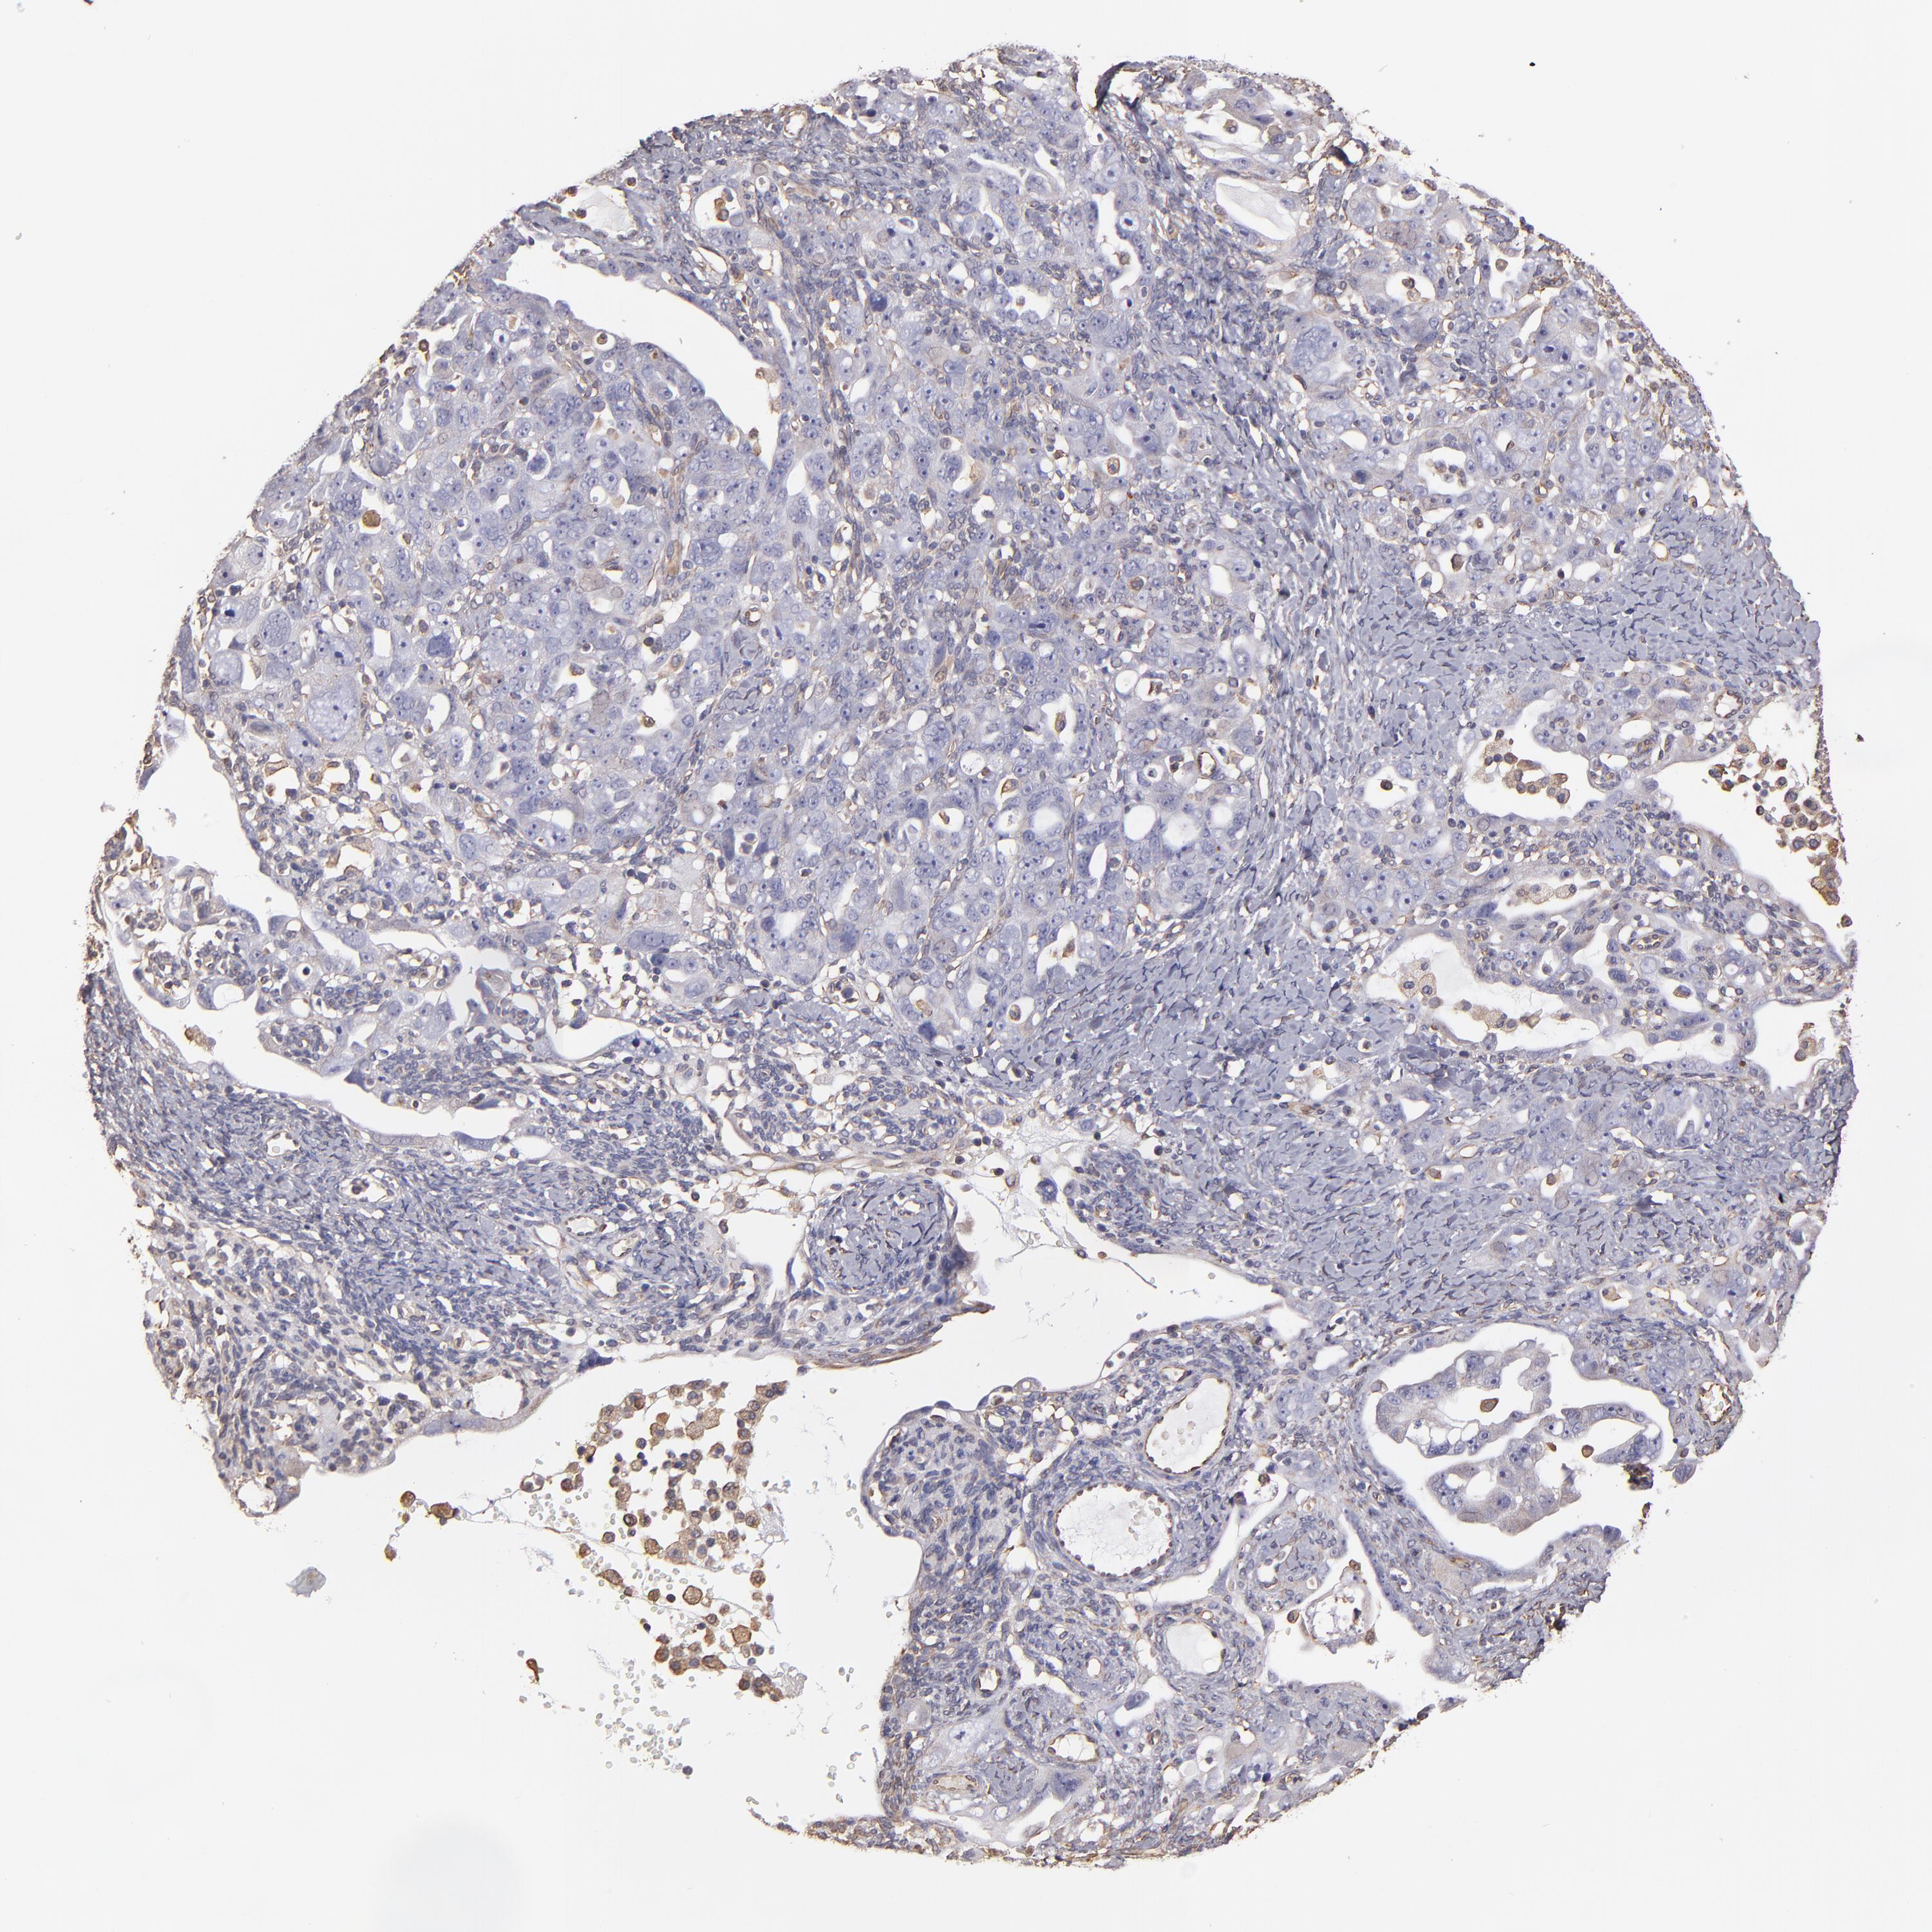

OVARIAN CANCER - Protein expressioni

A mouse-over function shows sample information and annotation data. Click on an image to view it in a full screen mode. Samples can be filtered based on level of antibody staining by selecting one or several of the following categories: high, medium, low and not detected. The assay and annotation is described here.

Note that samples used for immunohistochemistry by the Human Protein Atlas do not correspond to samples in the TCGA dataset.

Antibody stainingi

Antibody staining in the annotated cell types in the current human tissue is reported as not detected, low, medium, or high, based on conventional immunohistochemistry profiling in selected tissues. This score is based on the combination of the staining intensity and fraction of stained cells.

Each image is clickable and will lead to virtual microscopy that enables deeper exploration of all samples and also displays staining intensity scores, fraction scores and subcellular localization as well as patient and tissue information for each sample.

Antibody HPA002380

Staining

High

Medium

Low

Not detected

Intensity

Strong

Moderate

Weak

Negative

Quantity

>75%

75%-25%

<25%

None

Location

Nuclear

Cytoplasmic/membranous

Cytoplasmic/membranous,nuclear

Cystadenocarcinoma, serous, NOS

Cystadenocarcinoma, mucinous, NOS

Carcinoma, endometroid